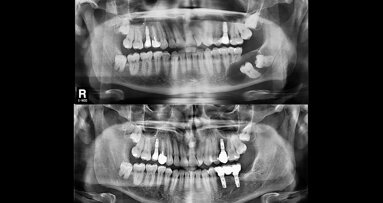

Con el objetivo de medir si las deficiencias se mejoraron por diferentes métodos y si OHRQoL de los pacientes cambió a través del tratamiento de rehabilitación oral, los investigadores compararon las prótesis con y sin implantes fijos y extraíbles.

En general, los datos indicaron que la rehabilitación oral resultó en una mejor apariencia y función masticatoria y por tanto, en una mejora significativa de la OHRQoL. Treinta y nueve de los 43 pacientes estudiados tenían puntuaciones OHIP inferiores después del tratamiento, pasando de una media de 77 puntos a 40 puntos, según el estudio.

Sin embargo, al comparar prótesis fijas versus removibles, no se encontró un efecto significativo en los resultados OHIP de los pacientes. Lo mismo aplica a los efectos de los implantes. Los pacientes tratados con implantes no difirieron significativamente en OHIP de los pacientes sin prótesis implantosoportadas.

Según los investigadores, los resultados pueden haber sido afectados por el limitado tamaño de la muestra y la gran variación entre los pacientes en el estudio. Una investigación futura tendrá que incluir una mayor muestra de pacientes con el fin de demostrar los beneficios significativos de los implantes, concluyeron.